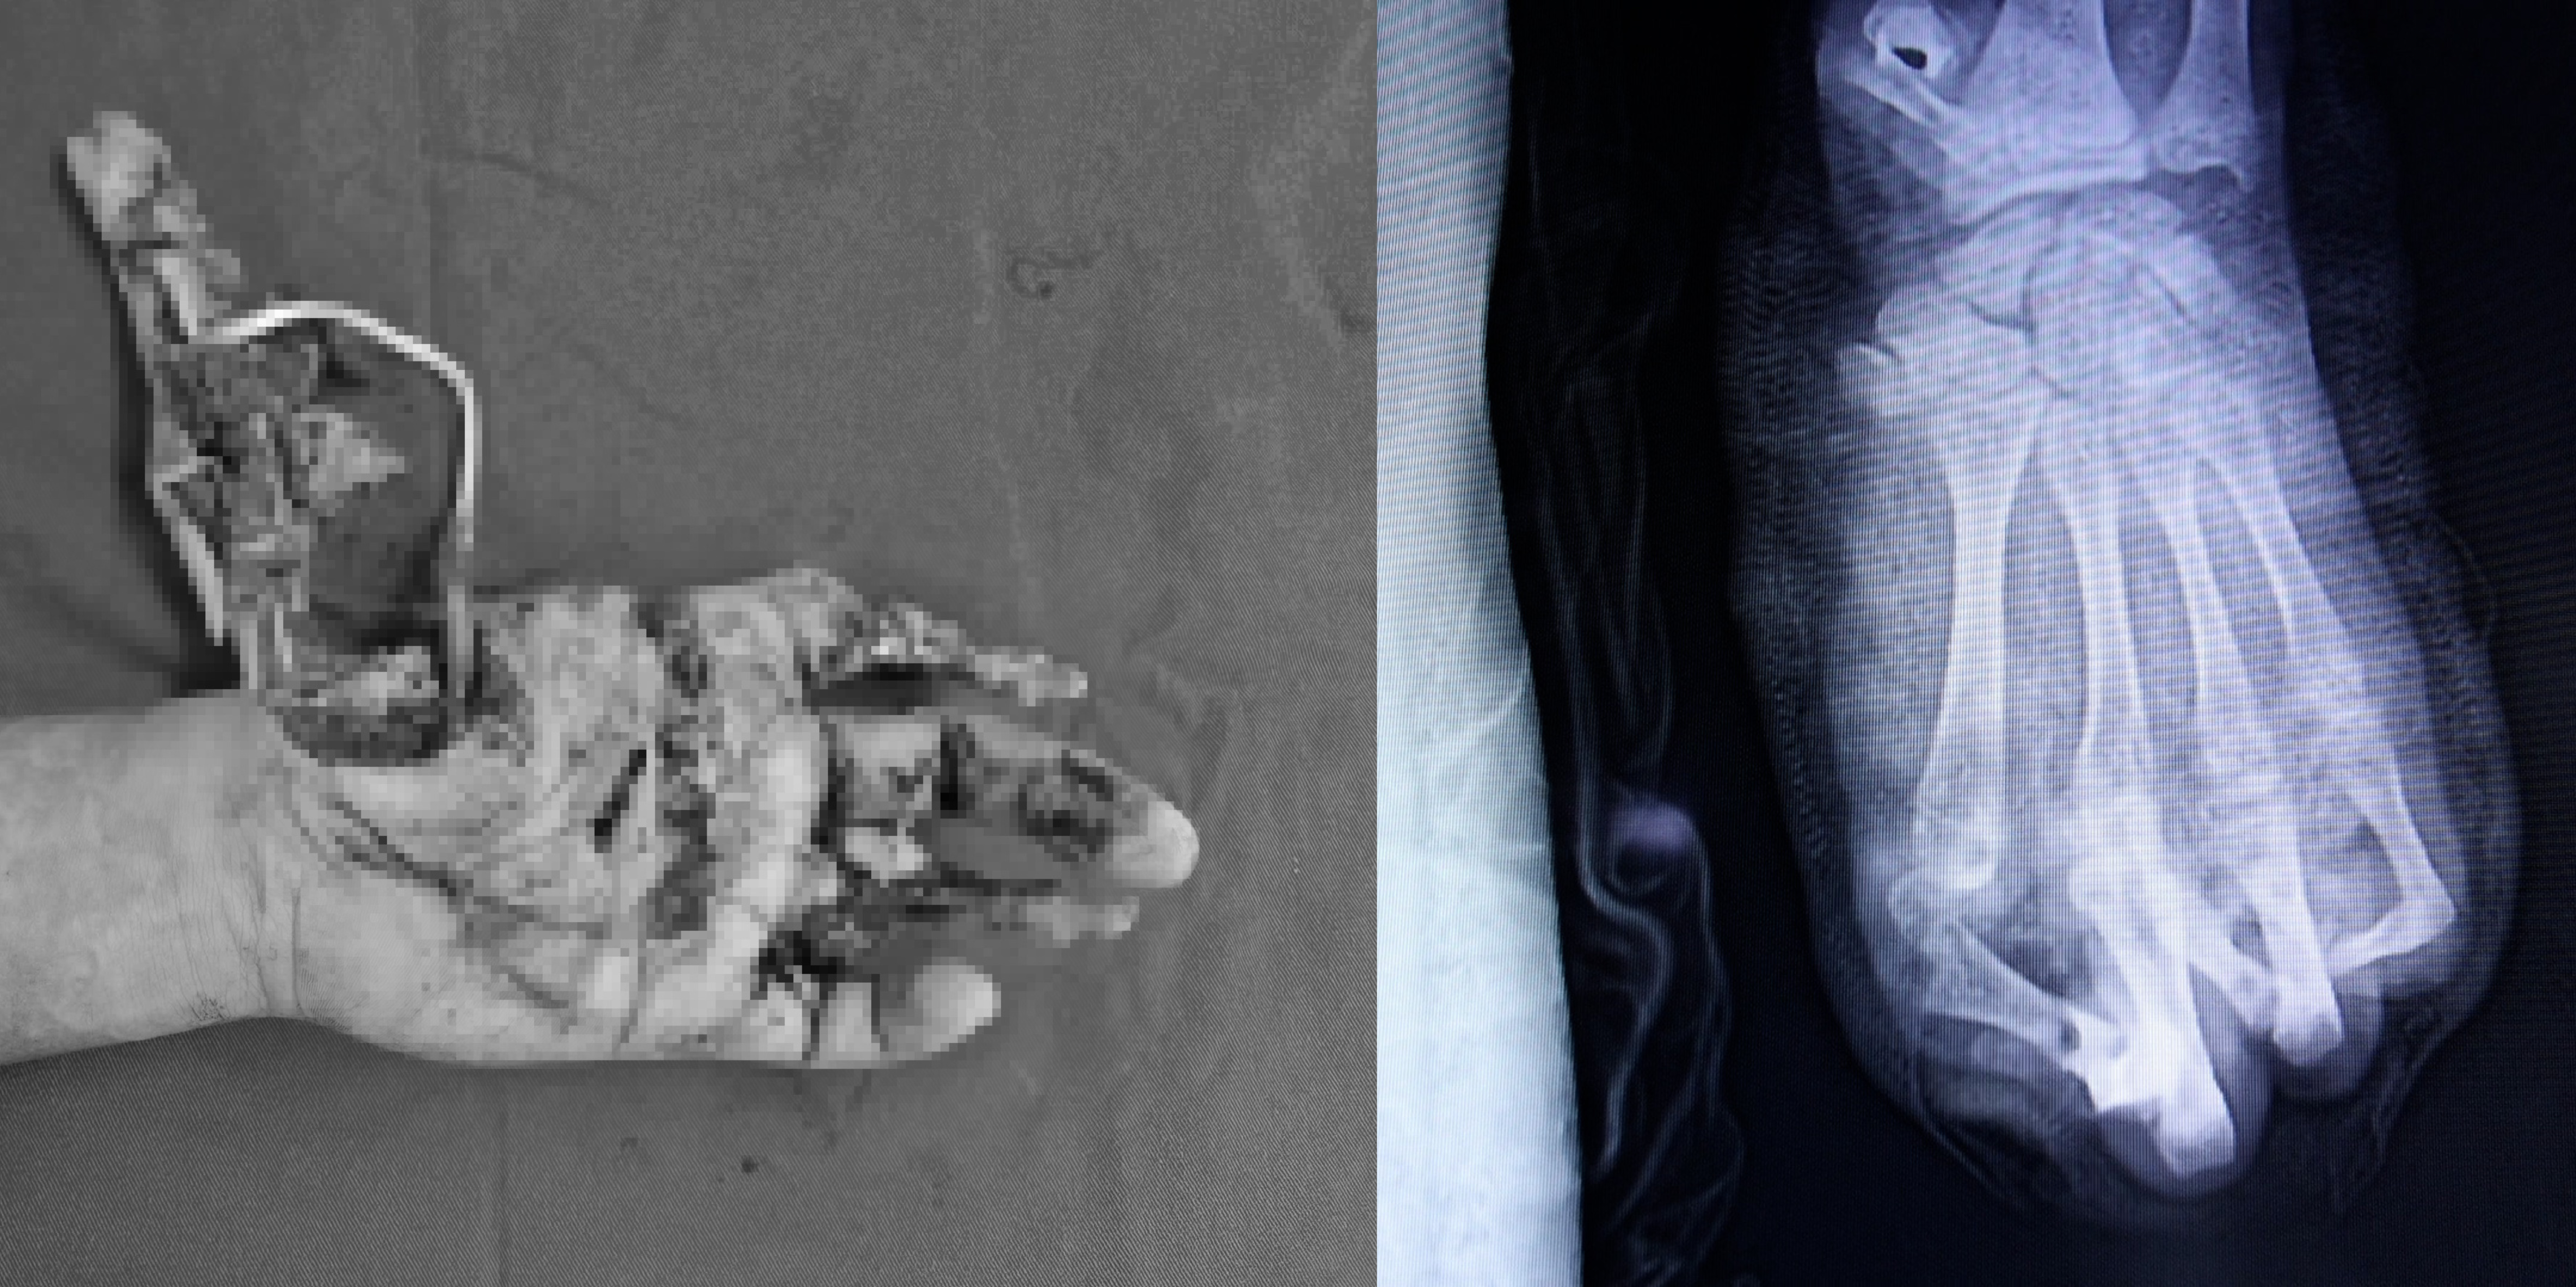

Vừa qua, Khoa Phẫu thuật Chi trên và Vi phẫu, Viện Chấn thương - Chỉnh hình, Bệnh viện TWQĐ 108 tiếp nhận một nam thiếu niên 15 tuổi bị tai nạn pháo nổ.

Người bệnh nhập viện sau tai nạn khoảng 3 giờ, trong tình trạng bàn tay trái dập nát gần như hoàn toàn, kèm theo vết thương phần mềm vùng đùi trái.

Tổn thương đặc biệt nghiêm trọng do pháo nổ. Ảnh: BVCC

Ngay sau khi tiếp nhận, người bệnh được cấp cứu và phẫu thuật khẩn trương. Tuy nhiên, do mức độ tổn thương quá nặng, ê-kíp chỉ có thể bảo tồn được 2 trong số 5 ngón tay.

Toàn bộ vùng gan tay và cổ tay bị dập nát nặng, khiến quá trình điều trị dự kiến kéo dài và cần nhiều lần phẫu thuật tiếp theo. Tiên lượng lâu dài, chức năng bàn tay chỉ có thể phục hồi một phần rất hạn chế.

Hiện tại, người bệnh đã được cắt lọc tổ chức dập nát, lấy bỏ các dị vật là mảnh pháo. Trong thời gian tới, các bác sĩ sẽ tiếp tục điều trị che phủ vùng hoại tử bằng vạt da và dự kiến sau vài tháng sẽ tiến hành phẫu thuật chuyển ngón chân để thay thế ngón tay cái đã mất. Dù vậy, người bệnh vẫn phải chấp nhận mất ít nhất 2 ngón tay vĩnh viễn.